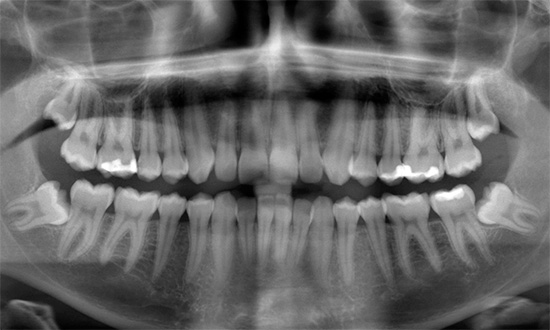

A estrutura da mandíbula inferior possui várias características que criam muitos obstáculos para sua simples remoção na região dos oitavos dentes inferiores. Por exemplo, se o oitavo dente superior quase sempre pode ser removido com sucesso e rapidamente do início ao fim com uma pinça, nos dentes inferiores isso não pode ser feito em 80-90% dos casos.

Devido à massa e densidade do osso da mandíbula, não é possível realizar uma aderência e balanço normais do dente (especialmente em caso de dificuldade em erupção, quando apenas 20 a 30% da coroa pode estar na superfície). Mesmo com uma coroa bem definida e sem cárie, o balanço do dente do siso inferior, localizado na espessura de um osso maciço, é muito, muito problemático, especialmente quando as raízes têm o número e a localização mais imprevisíveis na mandíbula.

De fato, as dobras e as rotações das raízes podem ser as mais incríveis. Freqüentemente, o dentista tem que lidar com duas ou mais raízes dobradas em ângulos diferentes, o que dificulta a extração de um dente que foi desapertado pelo cirurgião.

Por isso, antes de executar o procedimento de remoção, pode ser necessário fazer um raio-x de diagnóstico, permitindo que o dentista-cirurgião entenda com o que ele terá que lidar. Isso ajuda a evitar erros por parte do médico e também reduz o risco de possíveis complicações pós-operatórias.